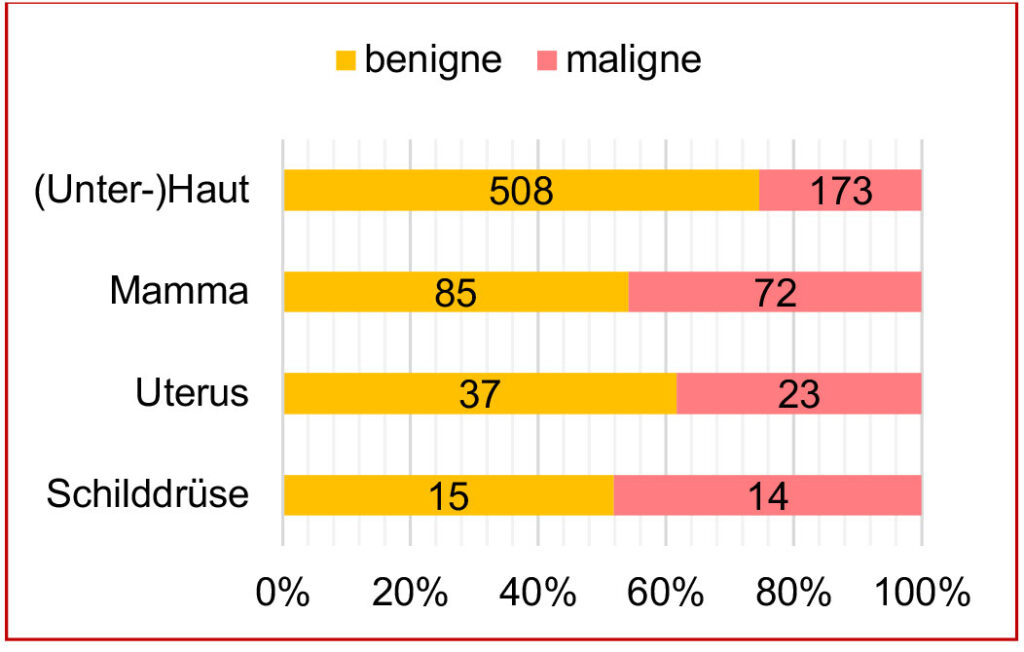

Um einen besseren Überblick über das Verhältnis von gutartigen zu bösartigen Tumoren zu erhalten, wurde dies in der nachfolgenden Abbildung schematisch für die am häufigsten eingesandten Tumoren aufgezeigt (Abb.3).

Abb. 3: Verteilung benigne/maligne Tumoren in den häufig eingesandten Entnahmelokalisationen

Bildquelle: Laboklin